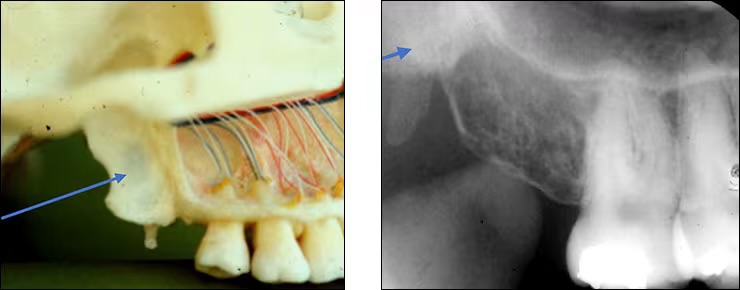

Coronoid process

Anterosuperior portion of the ramus

Seen when the patient’s mouth is open on posterior maxillary PA’s